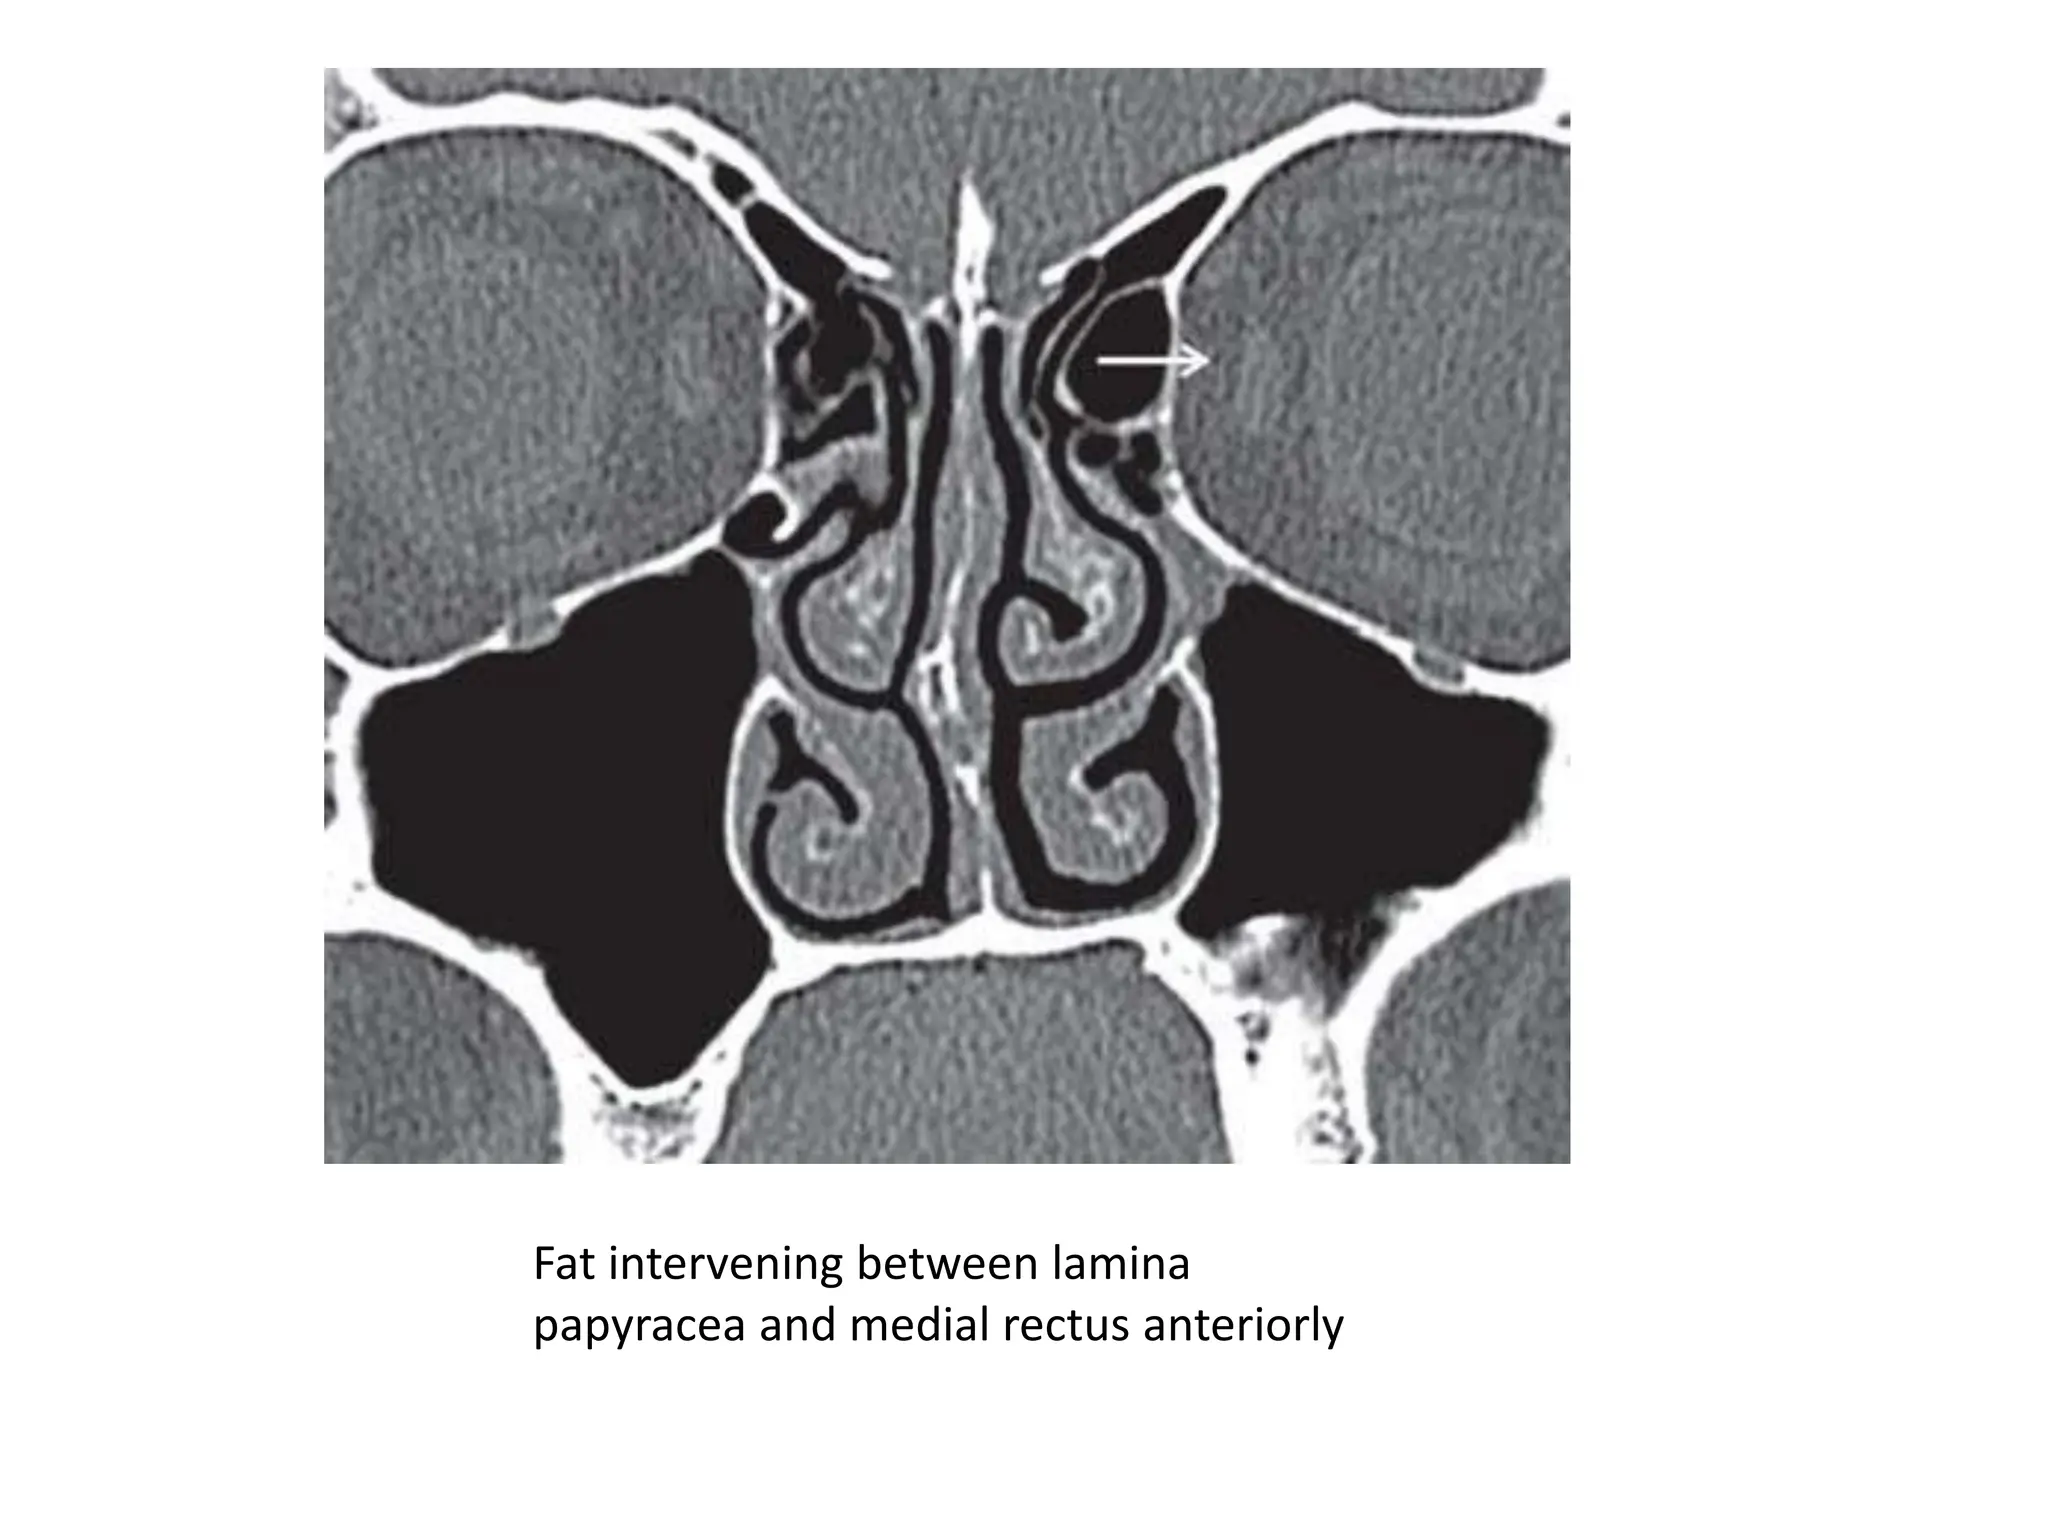

Fat intervening between lamina

papyracea and medial rectus anteriorly

• It is important to know that the medial rectus

is separated from the lamina papyracea by a

pad of fat anteriorly. However, more

posteriorly in the orbit this pad of fat is absent

and the medial rectus is in direct relation to

the lamina papyracea and therefore more

prone to injury